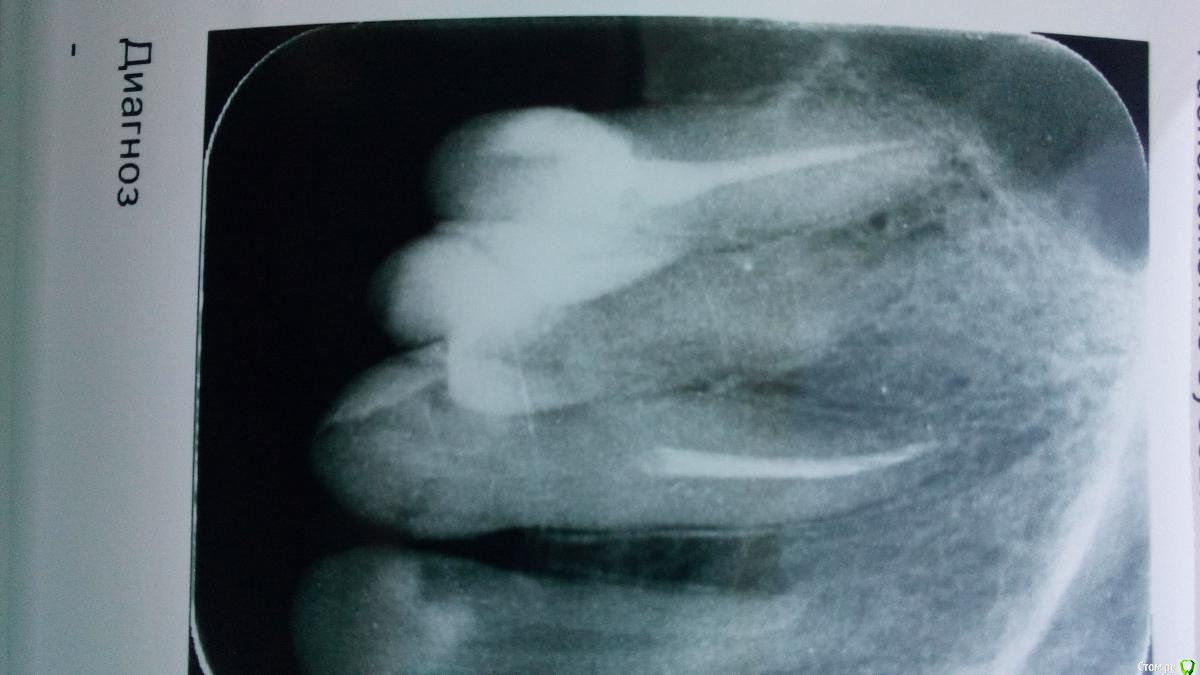

На7На Опубликовано 25 марта, 2018 Поделиться Опубликовано 25 марта, 2018 Здравствуете. Месяц назад была проведена операция цистэктомия, удаление 6, 7, 8 зубов. Киста была 28 мм х 23 мм. Перфорации не было как сказали, в пазуху не заходили. Киста ее прогибала. Зажило все хорошо. Швы сняли. Но больно нажимать на 5 зуб. Даже если языком сверху нажать больно. Не говоря уже что-то откусить. Сегодня сделала снимок. Зуб пролечен хорошо. Я не знаю что делать. Ссылка на комментарий

Irouil Опубликовано 25 марта, 2018 Поделиться Опубликовано 25 марта, 2018 (изменено) Все снимки в один день делали? Когда зуб подвергался лечению? Судя по первым, зуб нуждается в перелечивании. Чтобы говорить с максимальной уверенностью надо бы КТ сделать Изменено 25 марта, 2018 пользователем Irouil Ссылка на комментарий

На7На Опубликовано 25 марта, 2018 Автор Поделиться Опубликовано 25 марта, 2018 Все снимки в один день делали? Судя по первым, зуб нуждается в перелечивании. Чтобы говорить с максимальной уверенностью надо бы КТ сделатьДа снимки все сегодня. Перелечивать 5? Сегодня врач смотрел по снимку сказал хорошо пролечен, но он может давить на пазуху. Может поэтому боль? Ссылка на комментарий

Irouil Опубликовано 25 марта, 2018 Поделиться Опубликовано 25 марта, 2018 Да снимки все сегодня. Перелечивать 5? Сегодня врач смотрел по снимку сказал хорошо пролечен, но он может давить на пазуху. Может поэтому боль?Может, но месяц боли после операции - долговато. Реабилитация там должна была уже пройти. К сожалению плоскостные снимки обладают ограниченной информативностью. В такой ситуации как у Вас их можно интерпретировать двояко: не будь у Вас жалоб на боли, я бы тоже сказал, что наверное все хорошо. Я, все же, рекомендую 3д КЛ КТ. Верхнюю челюсть и верхнечелюстные пазухи, 12х8.5 хватит. Ссылка на комментарий